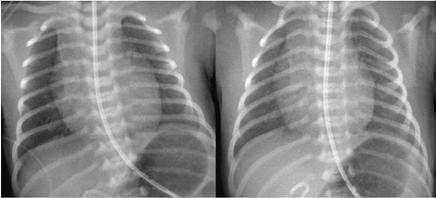

Historia actual: Neonato de 36 semanas y 2 días de edad gestacional, fruto de una 3ª gestación, nace mediante parto vaginal con ventosa tipo kiwi. Pre senta APGAR 9-10 para el primer y quinto minuto de vida. Al nacimien to presenta leve quejido sin trabajo respiratorio que progresa pasada 1 hora acompañado de tiraje intercostal (escala Silverman: 8) requiriendo traslado a UCI-Neonatal para monitorización y soporte respiratorio. Se inicia ventilación mecánica no invasiva (VMNI) con CPAP, con posterior escalada a modalidad BiPAP, logrando normosaturaciones y disminución de trabajo respiratorio con parámetros de protección pulmonar. Como factores de riesgo para el desarrollo de un cuadro infecioso/sepsis neo natal presenta estado de portador de estreptococo del grupo B materno desconocido y 28 horas de bolsa rota (con profilaxis antibiótica completa). Las serologías maternas son negativas y no se registra fiebre materna intraparto. Ante la presencia de un riesgo elevado de sepsis neonatal según la puntuación obtenida en la escala correspondiente (12,54/1.000 recién nacidos), se amplía estudio con pruebas complementarias. En las pruebas analíticas destaca la elevación de interleucina 6 (420,9 pg/ml) y, en las de imagen (radiografía de tórax), la presencia de focos difusos de aumento de densidad bilaterales, no presentes en la radiografía previa (Figura 1).

Figura 1. (Izq.) radiografía de tórax en proyección anteroposterior (AP) al ingreso en UCI-N para comprobación de sonda nasogástrica sin hallazgos significativos. (Der.) Radiografía de tórax AP a las 16 horas de vida donde se objetivan tenues focos de aumento de densidad de distribución difusa, alguno de ellos, como el localizado en campo superior izquierdo, con broncograma aéreo.

Figura 2. (Izq.) radiografía de tórax en proyección AP a las 36 horas de vida donde se objetiva neumotórax de nueva aparición (flechas azules) y una zona de hiperclaridad alrededor de la silueta cardíaca que sugiere importante neumomediastino (estrellas amarillas). (Der.) TC de tórax sin contraste intravenoso en ventana de pulmón que confirma la presencia de neumomediastino (estrella amarilla). Se objetivan focos de consolidación periféricos y bandas lineales de densidad aire paralelas y adyacentes a las vainas broncovasculares (flechas amarillas).